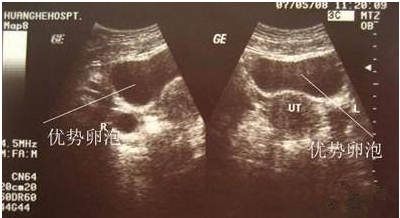

2.检测卵泡

卵泡大小的监测需利用阴道b超来完成,同时抽血检查E2值 (雌激素),调整用药量也是非常必要的。当二至三个以上的卵泡直径大于45px,且35px以上的卵泡数与E2值相当,便可注射人绒毛促性腺激素(HCG),促使卵泡成熟。在注射HCG后34~36小时取卵。